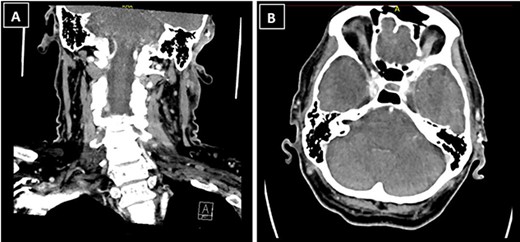

The patient’s case was discussed at the skin cancer multidisciplinary team meeting and he underwent imaging of the area for further evaluation, given the histological diagnosis. Computed tomography (CT) neck showed a 1.3 × 1.2 × 1.3-cm ill-defined soft tissue enhancement above the left external auditory canal involving the subcutaneous tissue and overlying skin (Fig. 3). There was involvement of the superior and superficial aspect of the parotid gland. CT thorax, abdomen and pelvis showed no evidence of distant metastases.

CT neck showed a 1.3 × 1.2 × 1.3-cm ill-defined soft tissue enhancement above the left external auditory canal involving the subcutaneous tissue and overlying skin; (A) coronal view; (B) axial view.